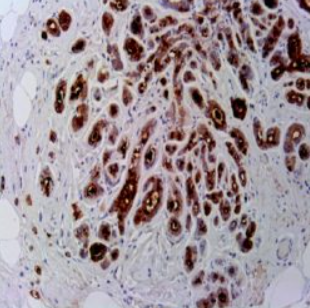

آنتی بادی PAX8  برند NOVOCELL یک آنتی‌بادی مونوکلونال با قابلیت شناسایی پروتئین PAX8 است که به عنوان یک فاکتور رونویسی کلیدی در تمایز و عملکرد اندام‌ های مختلف از جمله تیروئید، کلیه و دستگاه تناسلی نقش دارد. این آنتی‌ بادی برای استفاده در روش ایمونوهیستوشیمی روی بافت‌ های پارافینی بهینه‌ سازی شده و با پروتکل‌ های استاندارد دستگاه‌ های اتوماتیک مانند Ventana و Leica سازگاری کامل دارد. فرمولاسیون پایدار این محصول امکان شناسایی دقیق بیان PAX8 را در نمونه‌ های بافتی فراهم می‌کند.

• عملکرد ایده‌آل در IHC با رنگ‌آمیزی هسته‌ای

این آنتی‌ بادی به عنوان یک مارکر تشخیصی ارزشمند در پاتولوژی تومورهای تیروئید، کلیه و تخمدان کاربرد دارد. PAX8 در کارسینوم فولیکولار تیروئید، کارسینوم کلیوی، نفروبلاستوما و برخی تومورهای تخمدان بیان می‌شود و می تواند برای افتراق این نئوپلاسم‌ ها از متاستازهای سایر اعضا مورد استفاده قرار گیرد. این آنتی بادی در ترکیب با پانل‌های تشخیصی شامل TTF-1، mammaglobin و uroplakin، به تعیین منشا اولیه کارسینوم‌ متاستاتیک کمک می‌کند. کنترل مثبت آن نیز در بافت‌های تیروئید و کلیه طبیعی تعریف شده است.

Novocell PAX8 antibody enables precise nuclear staining for thyroid and renal tumors.